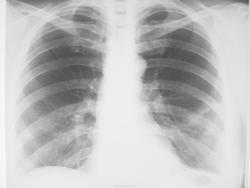

Пневмония? Локальный фиброз?

Пациентка около 65 лет с жалобами на слабость, повышение температуры в течение 2 дней направлена с д-зом ОРВИ. Пневмония?

Предыдущее исследование ОГК (ФЛГ) выполнялось в ноябре 2012 г

Я бы написала в заключении очаговую пневмонию в S4.

По мне - так нет. Пневмосклероз, может дисковидный ателектаз.

Примерно так + локальное усиление легочного рисунка, уплотнение главной междолевой плевры.

Никакой не фиброз, лечите пневмонию

Думаю, право на жизнь имеет версия двусторонней интерстициальной пневмонии. ОРВИ нижнего респираторного тракта.